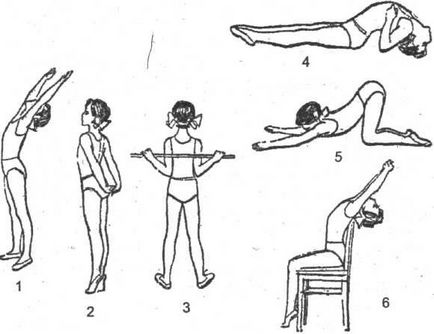

gyakorlat gyógytorna

Hozzájárulás a kezelésére kyphosis felnőtteknél a gyakorlatsort. megerősítését célzó körüli izmok a gerinc:

- Feküdjön a gyomorban. Kapunk mögött torna botot, és megnyomja azt a lapátok behajlítva, a könyök, a csukló. Elkezdjük görbe a törzs.

- Legyen négykézláb. A mellkas legyen megereszkedik a földre, fejét, karját behajlítva, a könyök. Ebben a helyzetben, feltérképezni legalább 40 lépésben.

- Feküdjön a gyomorban. Taken félre vagy feladja, hogy a súlyzó. Elkezdjük kiegyenesíteni a törzs.

A hatás lehet pozitív, fontos, hogy végre a gyakorlatokat helyesen és rendszeresen.